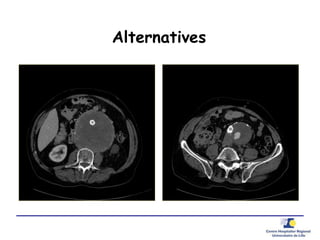

Alternatives

• Options alternatives